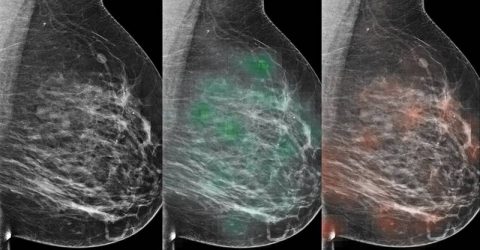

VÍDEO! Cuidado com o câncer de mama: especialista reforça exames e a relação entre sofrimento e a doença

Dr. Gentil Paiva abordou temas cruciais, como os sinais de alerta para o câncer de mama, e fez questão de reforçar que a atenção à saúde não deve se restringir apenas ao mês de outubro